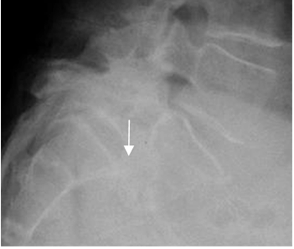

Fig 75. Inestabilidad.

A: Rx lateral neutra y B: Rx lateral en flexión. Anterolistesis GI-II de L4 sobre L5 y GI de L5, sobre S1, que no se modifica con la flexión.